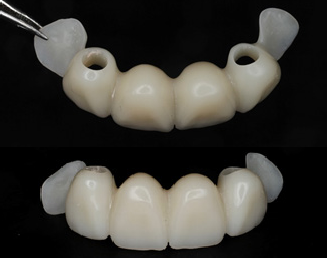

A milled PMMA temporary shell was designed with an ideal screw access and built-in critical zone for the emergence profile. The screw access area was designed to fit an the average diameter of a temporary abutment. This design decreases excessive adjustment of the shell.

The design of the temporary shell also included indexing wings which function to align the planned temporary restoration to the proper 3D orientation with perfect proximal contacts and no- centric occlusion restorations.

Since temp shells were already fabricated, we were ready to pick up our temporary prosthesis using non-engaging temporary abutments.

When picking up a multiple unit bridge on temporary abutments, make sure to never use flowable due to possible shrinkage of the material and only use self-curing no-shrinkage resin based material (Integrity).